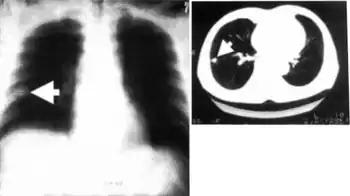

Dirofilariasis is an infection by parasites of the genus Dirofilaria.[1] It is transmitted through a mosquito bite; its main hosts include dogs and wild canids. These can give rise to granulomas in the pulmonary artery. Some common symptoms include cough, fever and pleural effusion. It may also appear on X-rays of the chest.[2]